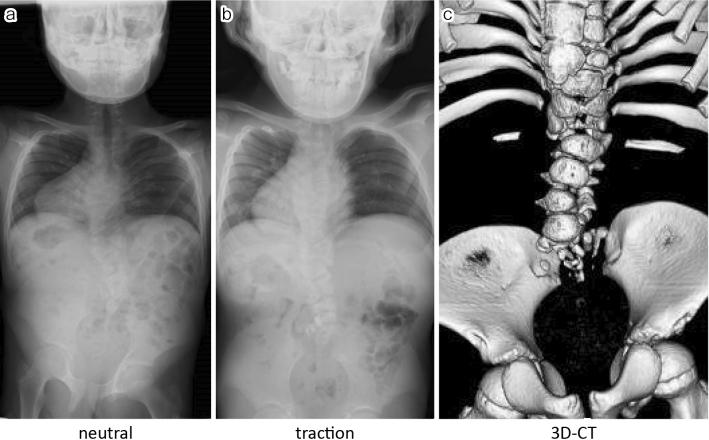

Case 1. A 10-year-old male underwent T8-S posterior fixation followed by multiple augmentations using allografts at the lumbosacral junction for delayed union. All additional procedures with bone graft using a posterior approach failed to achieve bone union; however, additional rigid fixation at the pubic symphysis resulted in a successful lumbosacral bone union. Case 2. A 6-year-old male underwent vertical expandable prosthetic titanium rib (VEPTR) surgery with multiple rod extension procedures. Subsequently, at the age of 10 years, a combined two-stage anterior (L1-3) and posterior (T8-iliac) fixation with T9 hemivertebrectomy was performed. As a result of subsequent nonunion with screw loosening, additional rigid fixation at the pubic symphysis was performed 1 month after posterior fixation. Bone union was finally achieved 1 year after all the surgical interventions.

病例1。一名10岁男性接受了T8 - S后路固定术,随后在腰骶部交界处使用同种异体骨进行了多次增强手术以促进延迟愈合。所有采用后路植骨的额外手术均未能实现骨愈合;然而,耻骨联合处的额外坚强固定导致腰骶部成功骨愈合。病例2。一名6岁男性接受了垂直可扩张人工钛肋骨(VEPTR)手术及多次棒延伸手术。随后,在10岁时进行了两阶段联合前路(L1 - 3)和后路(T8 - 髂骨)固定并进行了T9半椎体切除术。由于随后出现螺钉松动导致不愈合,后路固定术后1个月在耻骨联合处进行了额外的坚强固定。在所有手术干预1年后最终实现了骨愈合。